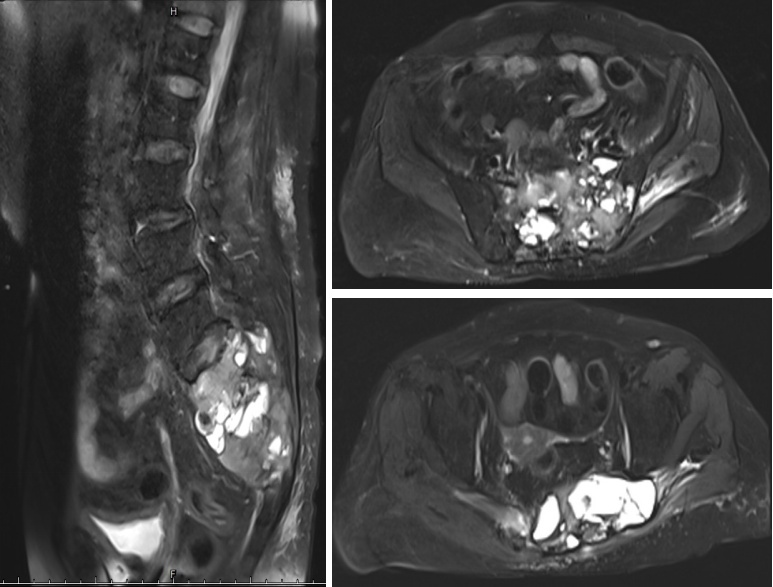

患者术前影像资料显示全骶骨、左侧骨盆及臀部肌肉广泛受累

面对手术的挑战,术前必须做好精密的手术方案,尹军强教授组织了多次的多学科会诊。在征得患者及家属同意后,专家团队决定在机器人微创辅助下行骶前肿瘤分离,结扎肿瘤血供,减少后路切除肿瘤手术时的大出血风险。同时,在后路骨科机器人的辅助下,进行全骶骨+左侧部分骨盆精准切除、重建,尽可能降低肿瘤复发风险。